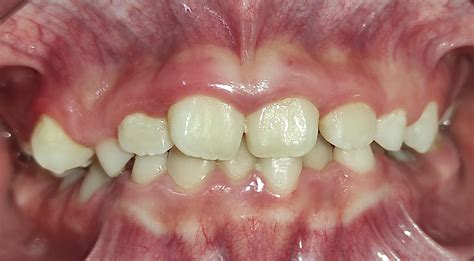

La hipoplasia maxilar, también conocida como subdesarrollo del maxilar superior, es una condición caracterizada por un desarrollo insuficiente del hueso maxilar superior. Este subdesarrollo puede causar problemas tanto de alineación dental como de apariencia facial. Las personas con esta afección suelen presentar:

- Una mandíbula que sobresale en comparación con la parte superior del rostro.

- Mordida cruzada o problemas de alineación dental.

- Mordida Clase III: los dientes inferiores sobresalen notablemente por delante de los dientes superiores.

- Perfil facial: el mentón suele ser prominente y la zona del labio inferior puede verse hundida.